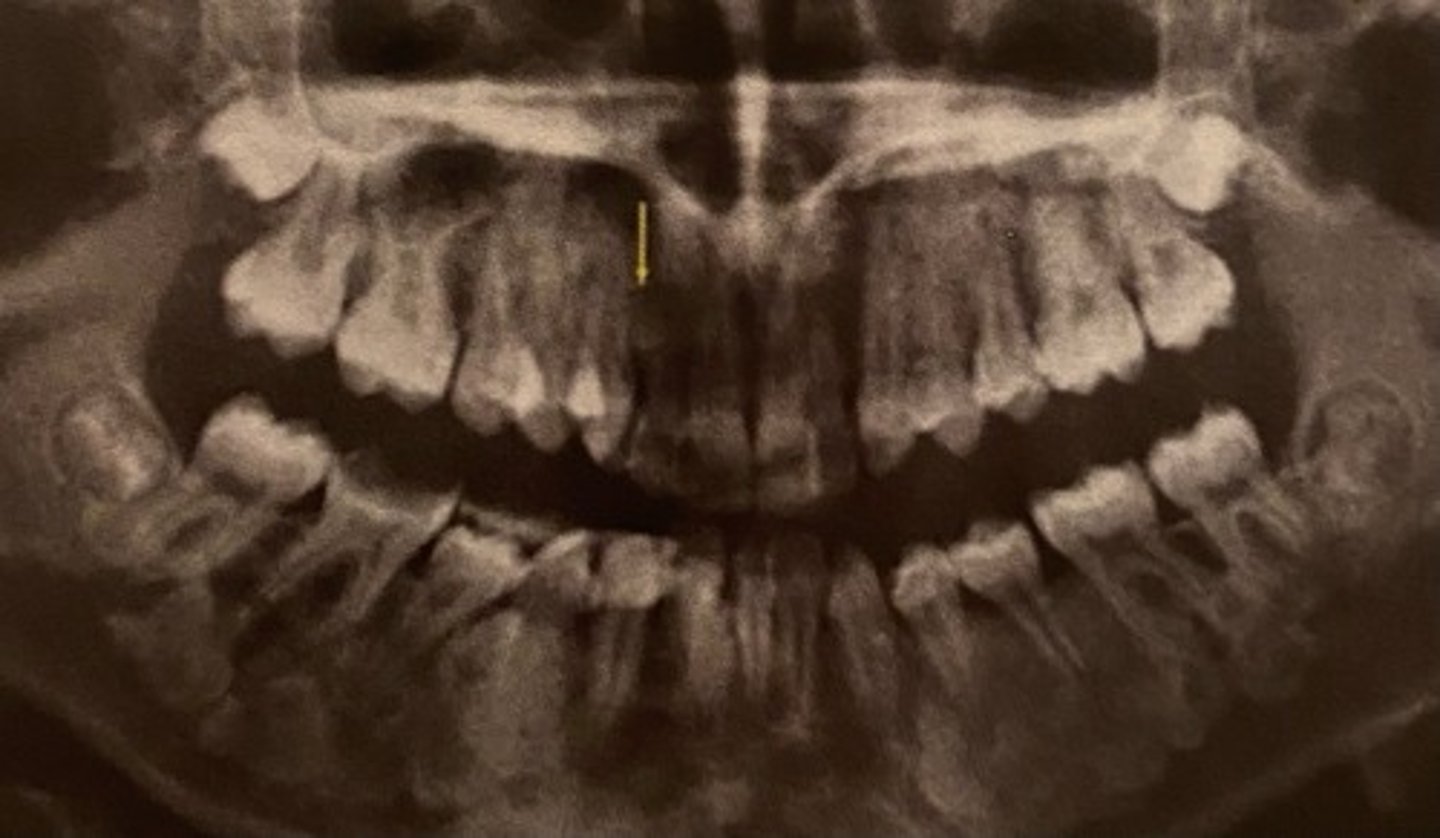

Most common single supernumerary tooth?

Mesiodens

Location of Mesiodens?

Btwn maxillary centrals